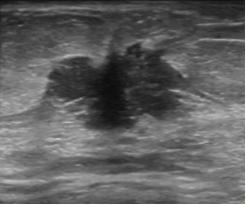

结节边缘为微小分叶,术后病理为恶性

结节的边缘成角,是恶性的表现